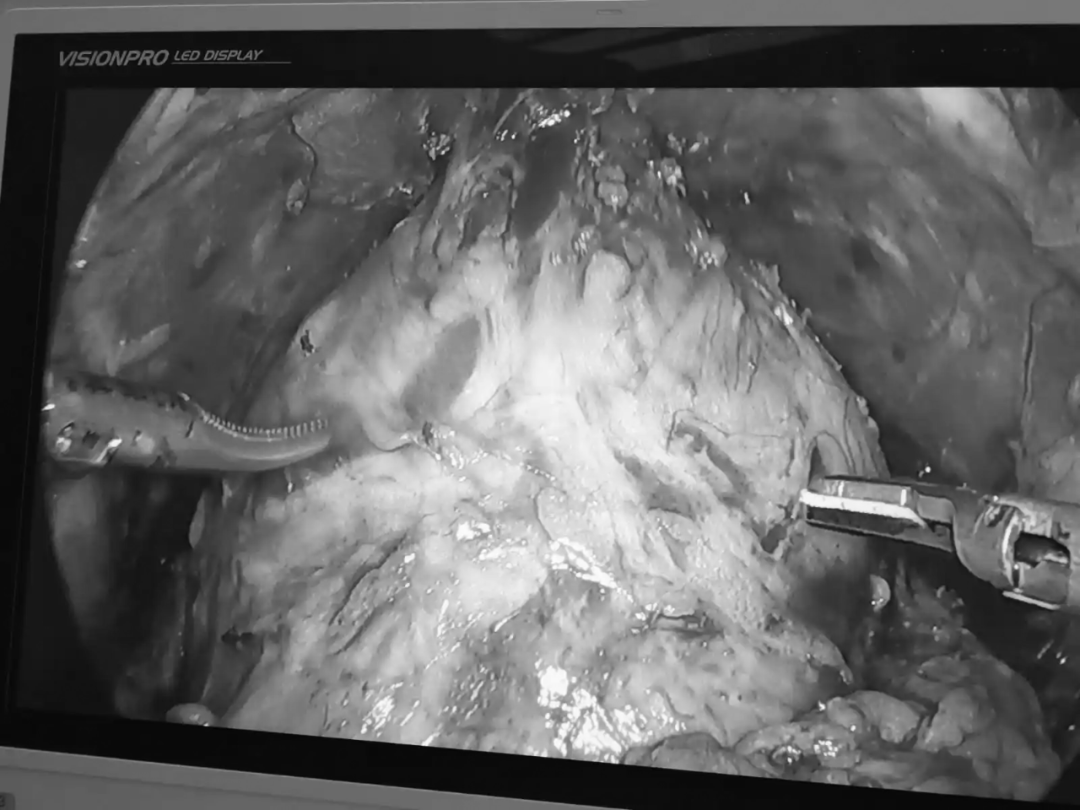

前列腺癌为男性泌尿生殖系统中最常见的肿瘤,位居我国男性恶性肿瘤发病率的第六位,为男性恶性肿瘤死亡率的第七位,且发病率与死亡率均呈上升趋势。目前首选治疗方式为腹腔镜下前列腺癌根治术,但术后可能出现尿失禁及性功能障碍等并发症。保留性神经的腹腔镜前列腺癌根治术是一种用于治疗前列腺癌的先进手术方法,术中在彻底切除肿瘤的同时也能最大程度地保留前列腺周围的重要神经和血管结构,尤其是勃起神经血管束(NVB)和背深静脉复合体(DVC),相较于传统的手术方式,能有效降低患者术后出现勃起功能障碍和尿失禁的风险,从而提升患者的生活质量,有助于缓解患者术后可能出现的焦虑和抑郁症状,同时腹腔镜手术创伤小、恢复快,利于推动患者的早期恢复。

图片